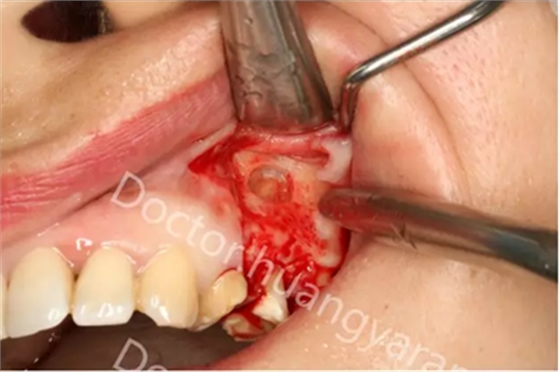

拍攝根尖片檢查,24、25牙根充到位,但考慮到可能是治療過(guò)程中消毒不到位導(dǎo)致,所以重新對(duì)25牙做根管治療,但酸痛感無(wú)減輕,于是考慮到根尖骨穿孔的可能性,與患者溝通后做診斷性翻瓣,翻瓣后發(fā)現(xiàn)根尖處無(wú)頰側(cè)骨板直接暴露,當(dāng)即行根尖切除術(shù),對(duì)位縫合,經(jīng)兩個(gè)月恢復(fù)根尖已無(wú)酸痛感!